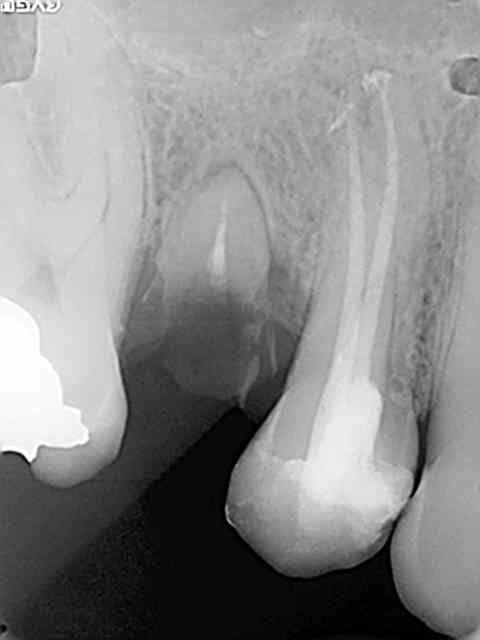

Une petite de ce matin et une plus ancienne, toutes les deux avec la même "recette".

Vous remarquerez en zoomant sur celle de ce matin comme le matériau a bien "squirté" en mésial. Devant de tels résultats, je ne vois pas pourquoi j'irai m'emmerder avec un system B...

Ah tu es passé à côté du 3ème canal sur la prémol de droite choixpeau....